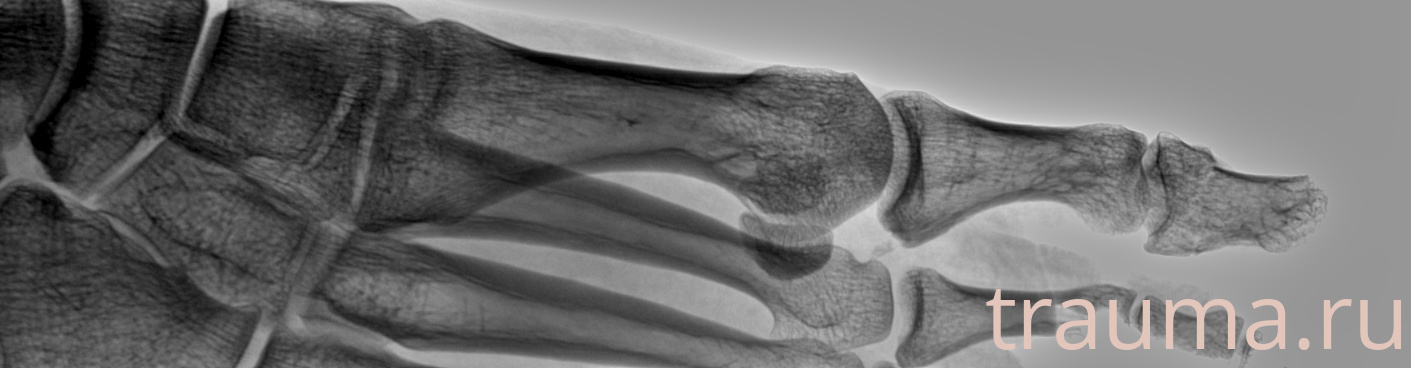

Рентген на дому: по вашему адресу приезжает врач-рентгенолог, травматолог-ортопед с мобильным рентгеновским аппаратом, проводит диагностику травмы или заболевания, делает необходимые рентгенограммы, дает рекомендации по дальнейшему лечению. Получить качественные снимки в домашних условиях возможно благодаря уникальной методике, разработанной МосРентген Центром для института  Склифосовского